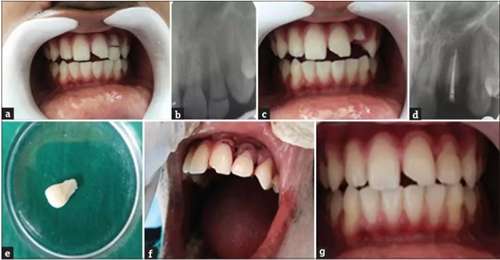

病例1

患者,男,23歲,因跌倒在地導(dǎo)致左側(cè)上頜側(cè)切牙復(fù)雜冠折。患牙無(wú)明顯松動(dòng),口內(nèi)和口外檢查無(wú)明顯軟組織創(chuàng)傷。牙齒22出現(xiàn)EllisⅢ級(jí)牙折,牙折線(xiàn)從舌側(cè)中1/3至舌側(cè)齦下2mm處。折斷部分松散地附著在牙齒上。

a. 術(shù)前口內(nèi)照片;b. 術(shù)前根尖片;c. 拔除牙齒折斷片;d. 根尖部分充填;e. 牙齒折斷片;f. 折斷片再?gòu)?fù)位;g. 軟組織縫合;h. 術(shù)后2年。

根尖片顯示牙根發(fā)育完全,無(wú)嵌入?;颊呦MA粞例X,計(jì)劃給予患者根管治療和樁核修復(fù)。

局部麻醉后,輕輕去除患牙折斷部分,并放入生理鹽水中防止脫水和變色。仔細(xì)檢查折斷片與患牙的適應(yīng)性。根尖定位儀確定根管工作長(zhǎng)度并拍攝根尖片確認(rèn),擴(kuò)孔鉆進(jìn)行根管冠部擴(kuò)大,根管在工作長(zhǎng)度上擴(kuò)大到60#。在制備過(guò)程中使用約3%的次氯酸鈉沖洗、將根管用指尖干燥并用根管封閉劑封閉,牙膠尖充填根管,根管口臨時(shí)修復(fù)體密封。牙髓治療完成后的第二天,局麻下翻瓣,暴露腭側(cè)齦下斷緣。去除根管冠部2/3部分的牙膠,預(yù)備樁道。試?yán)w維樁,并調(diào)到合適的長(zhǎng)度。對(duì)折斷部分的牙折片髓室部分進(jìn)行預(yù)備以容納纖維樁的冠部及核。然后用37%磷酸酸蝕,沖洗、干燥后涂布粘結(jié)劑。使用雙固化樹(shù)脂粘結(jié)劑(RelyX, 3M, )將樁置于根管中,經(jīng)過(guò)適當(dāng)?shù)纳{(diào)匹配后,冠部折斷片內(nèi)部進(jìn)行酸蝕并用可流動(dòng)復(fù)合樹(shù)脂粘結(jié)到牙齒上。最后,皮瓣復(fù)位,縫合,檢查咬合并給予患者術(shù)后指導(dǎo)。術(shù)后1月,3月,6月,1年,2年進(jìn)行臨床和影響學(xué)檢查,牙齒愈合良好。